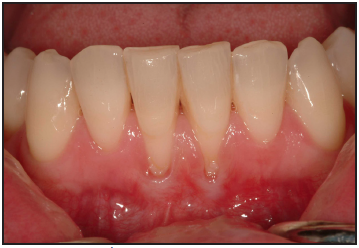

Gingival recession is defined as the reduction of the height of the marginal gingiva to a location apical to the cementoenamel junction, resulting in root surface exposure (Figure 11). Gingival recession can be precipitated by many factors including increasing age, gender, and anatomical factors. Toothbrushing technique, frequency, duration, force of brushing, and the hardness of toothbrush filaments may also contribute to gingival recession.36

Gingival recession - reduction of the height of the marginal gingiva to a location apical to the cementoenamel junction, resulting in root surface exposure.

Figure 11 – Gingival Recession

Figure 11